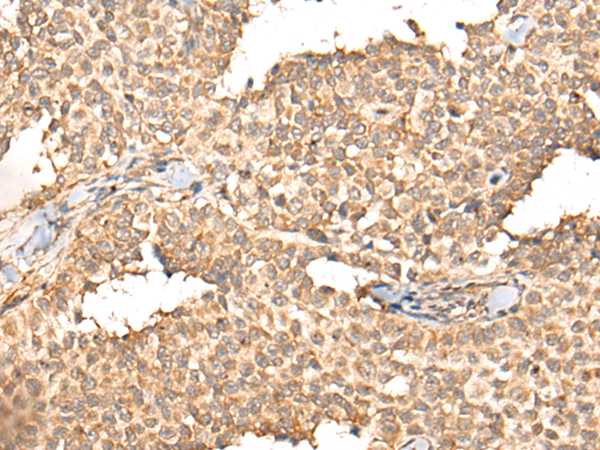

IHC positive control: |

Human liver cancer and human ovarian cancer |

IHC Recommend dilution: |

25-100 |